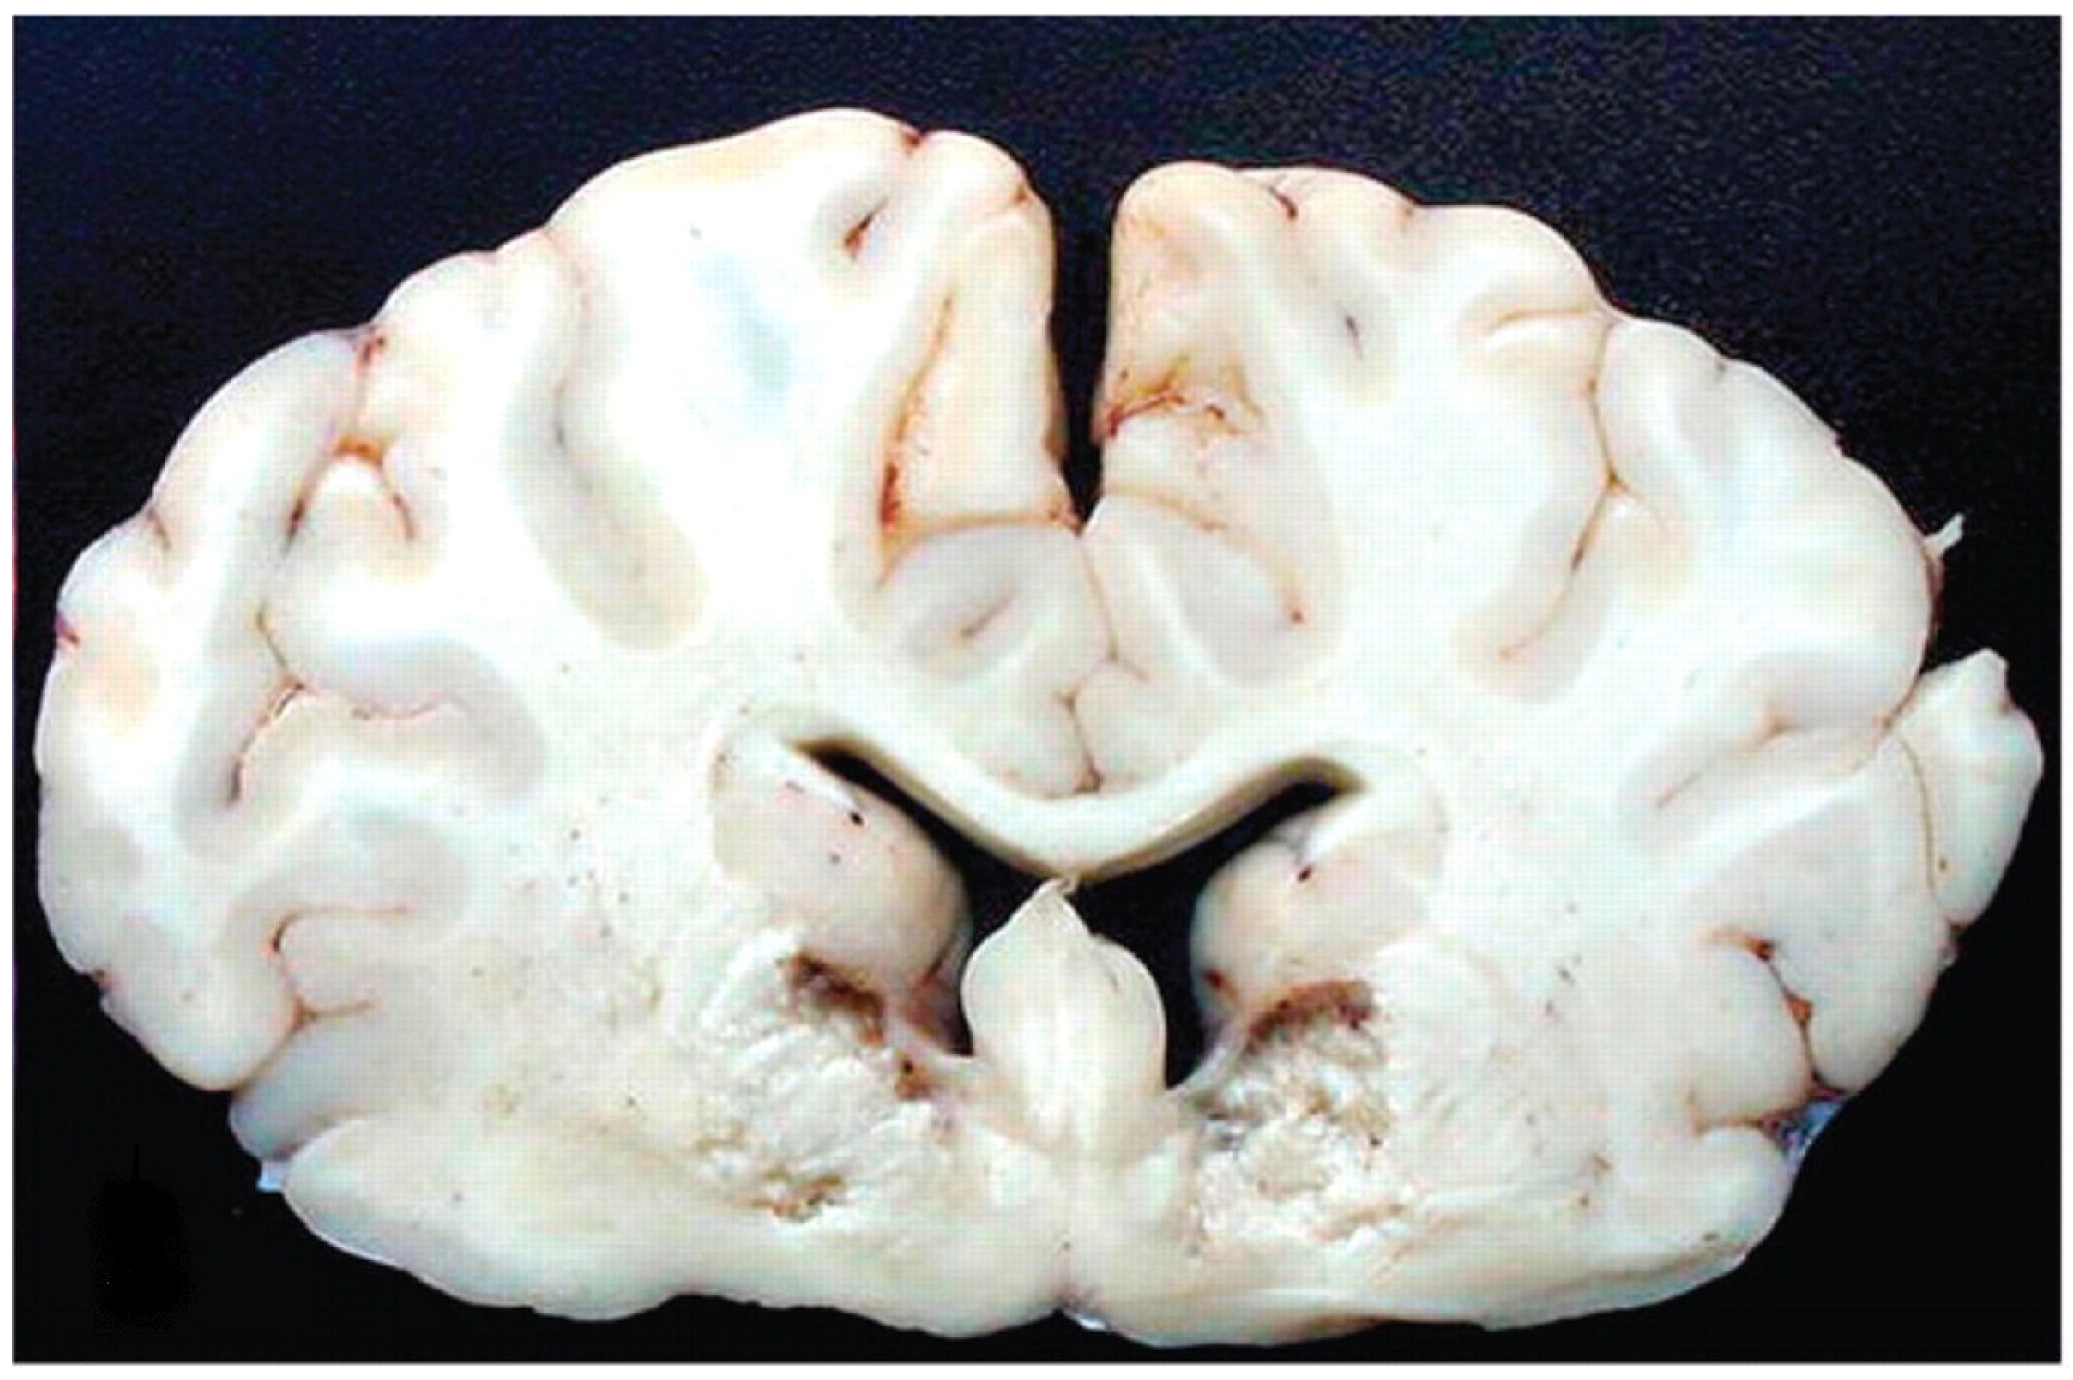

Clostridium perfringens type D is the agent of enterotoxemia, commonly called overfeeding disease or pulpous kidney disease. In Brazil, there are reports of diseases in cattle causing mortality and considerable damage to Brazilian agribusiness [6,27,28,29,30,31,49,50]. Changes in the rumen microbiota as a result of sudden changes in diet, provision of diets rich in carbohydrates and low in fiber, among other factors, lead to the multiplication of the agent in logarithmic proportions, producing large amounts of epsilon toxin in the form of protoxin, being converted into a lethal protein by the action of digestive trypsin or by secondary toxins from C. perfringens. The activated toxin acts on the intestinal epithelium, causing increased vascular permeability, and, upon reaching the blood circulation, reaches organs such as the brain, kidneys, lungs, liver and heart, where it binds to specific receptors on endothelial cells, leading to degeneration. of these cells. With increased vascular permeability, extravasation of fluids and proteins occurs into the perivascular space, with consequent edema. When it occurs in brain tissue, it is called eosinophilic proteinaceous perivascular edema or microangiopathy [44,45,46,47,48,49,50].

In cattle in Brazil, under natural conditions and in most cases, the death of animals occurs during the first six to 18 h, but if they survive for more than 36 to 48 h, necrosis of the brain tissue occurs, known as focal symmetric encephalomalacia (Figure 7). The most common clinical form is super-acute, with death within four to eight hours. Neurological changes such as opisthotonus and pedaling movements can be observed, as well as respiratory changes such as tachypnea and pulmonary edema. At necropsy, findings may not be evident, but in some cases, hydrothorax, hydropericardium, hydroperitoneum, pulmonary edema and cerebellar hernia are found. Histopathological lesions are neurological lesions restricted to histopathological findings of eosinophilic proteinaceous perivascular edema or microangiopathy and focal symmetric encephalomalacia [6,27,28,29,30,31,49,50,51].

Figure 7. Focal symmetrical encephalomalacia. This animal developed progressive neurologic signs that became severe 8 days after inoculation, at which time the calf was euthanatized [49]. Reprinted with permission from Ref. [49].